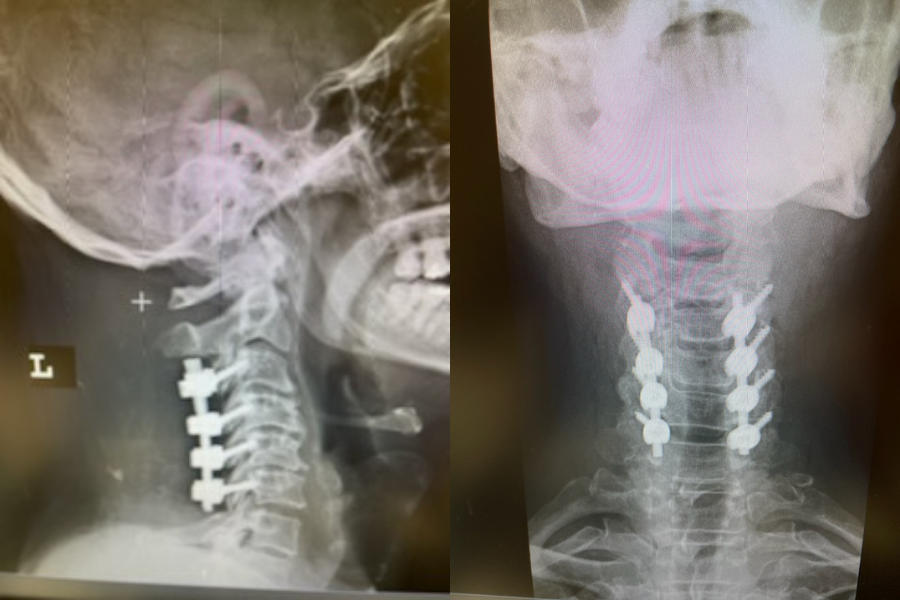

(3) Post operative AP and lateral cervical x-ray demonstrating good placement of hardware and alignment.

Patient did well from surgery with reduced pain in left shoulder and no further leak.(Fig. 3)